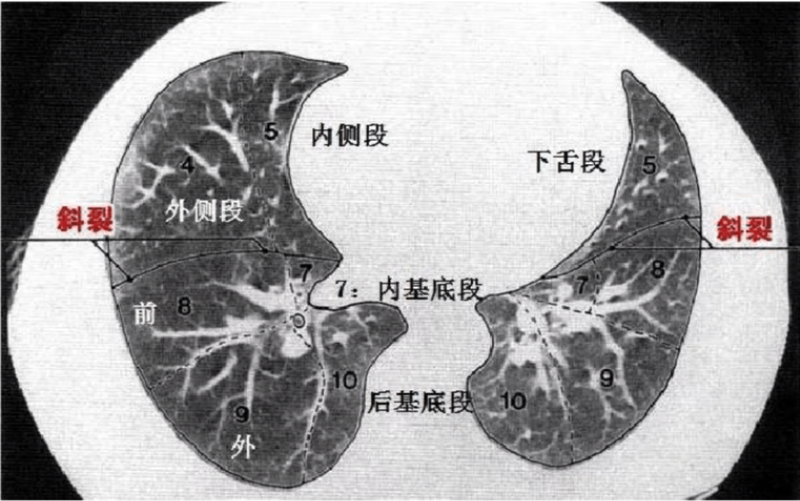

中叶: S4:外段;S5:内段;。

下叶: S6:背段;S7∶内基底段;S8:前基底段;S9:外基底段;S10:后基底段。

上叶:S1+2:尖后段;S3:前段;S4:上舌段/舌叶上段;S5:下舌段/舌叶下段。

下叶:S6:背段;S7+8:前内基底段;S9:外基底段;S10:后基底段